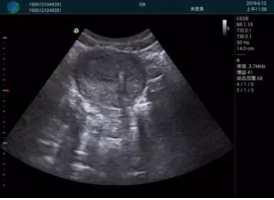

M20查看:囊內(nèi)回聲均勻,邊界清晰,囊壁光滑

M20引導(dǎo)抽吸術(shù)后囊腫消失,原區(qū)域空腔形成,脂肪層與腺體層架構(gòu)發(fā)生改變

超聲引導(dǎo)下可視化人流是技術(shù)安全性的保障,一般對人流術(shù)設(shè)備預(yù)算不高,M20具備婦產(chǎn)科軟件包,且穿透力圖像質(zhì)量好,既滿足人流引導(dǎo)需要,也可用于床旁超聲的需求。